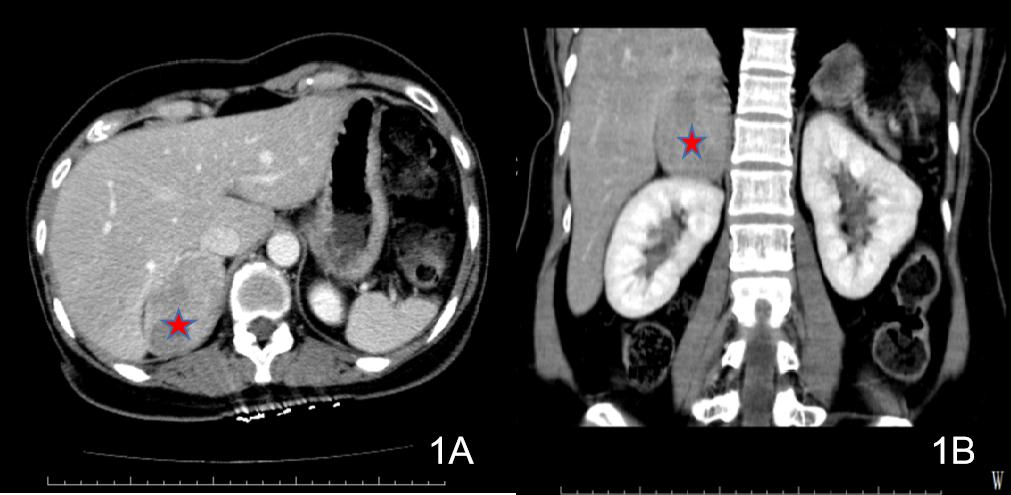

诊治经过如下。入院后查:HGB 81 g/L;生化十项(住院):CR 123.1 μmol/L,GLUC 22.22 mmol/L;心肌损伤标志物:TnI >50.0 ng/mL,MYO 377.45 ng/mL,CKMB Ⅱ 80.86 ng/mL;血气分析:pH 7.361,PCO2 33.5 mmHg,PO2 144.0 mmHg,BEb −5.0 mmol/L。予吸氧、积极补液扩容及输注悬浮红细胞(6U)、控制血糖等治疗。2021-06-18凌晨复查CT提示“左侧肾上腺区占位范围较前相仿,腹腔内积液较前增多”(见图 3)。2021-06-18早上复查BCA示Hb回升至115 g/L。

| 图 3 2021-06-18患者2腹部CT(腹腔积液较前增多) |